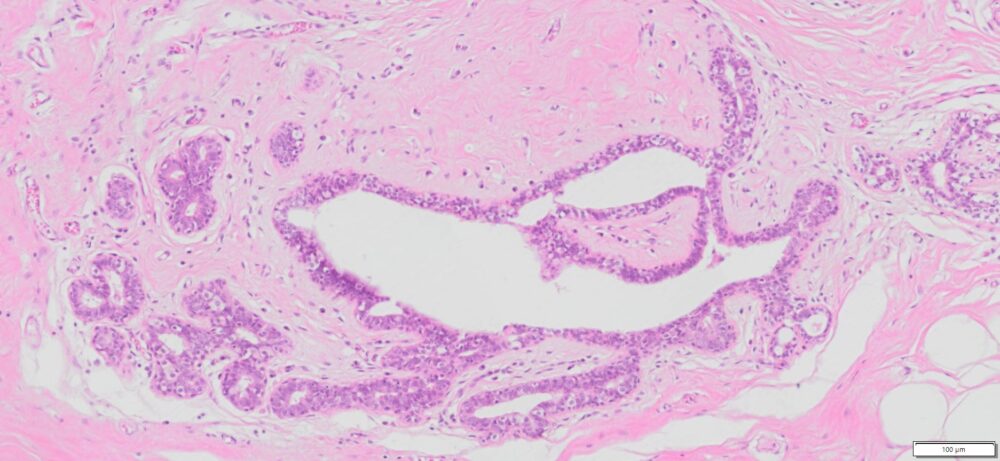

| SKU# | Organ | Pathology Diagnosis | Gender | Age | Grade | TMN | Thickness | IHC Tested |

| HuPS-02006A | Human Breast | Normal breast tissue | Female | 75 | — | — | 5um |

Human tissue was fixed in formalin immediately after excision and embedded in paraffin. The tissue sections were 5 µm in thickness and mounted each on positively charged glass slides.